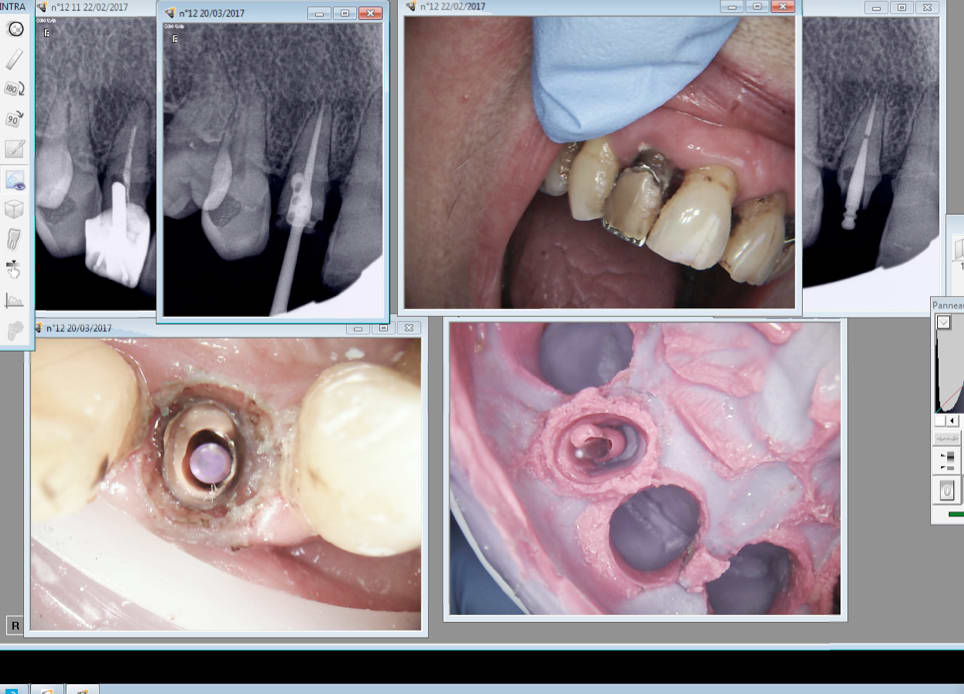

Capture d écran 2017 03 20 19.26 - Eugenol

Capture d écran 2017 03 20 19.29 - Eugenol

Quand j'ai commencé ce cas je me suis dit mais pourquoi tu t'emmerdes ? -)))

Pourquoi veux tu toucher du métal ? C'est pas un bistouri électrique !